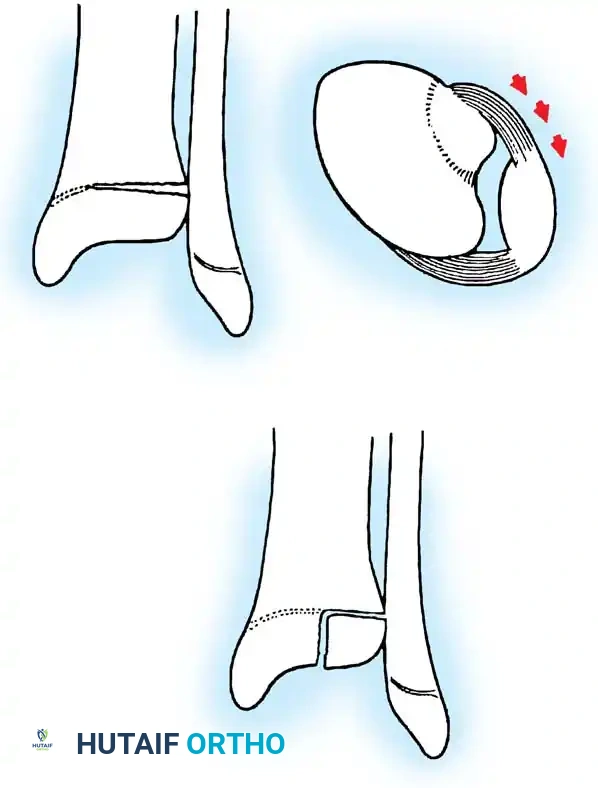

- Type III Fractures: These present in two distinct patterns:

- An intra-articular fracture analogous to an adult tibial plateau fracture.

- A fracture propagating through the tibial tuberosity physis, extending proximally across the epiphysis and into the knee joint.

Fig. 33-174: Salter-Harris type III fracture of the proximal tibia. A, Fracture analogous to a tibial plateau fracture. B, Fracture through the tibial tuberosity and across the epiphysis into the knee joint.

These tuberosity-extending fractures are not simple avulsions; they are massive, tongue-type Salter-Harris III injuries that lift the entire tibial tuberosity and anterior proximal physis superiorly. They almost universally necessitate open reduction and internal fixation (ORIF) to restore joint congruity and extensor mechanism continuity.

- Type IV Fractures: These cross both the epiphysis and metaphysis. They carry a high risk of growth arrest and joint incongruity. Stress radiographs are invaluable for diagnosing associated ligamentous instability, which may masquerade as a simple non-displaced physeal fracture.

Fig. 33-176: Physeal fracture with major ligamentous injury. A, Nondisplaced Salter-Harris type IV fracture. B, Stress radiograph shows fracture displacement and medial joint line opening, implying tibial collateral ligament injury. C, Intraoperative view during ORIF.

Triplane Variants: Variants of Salter-Harris III and IV fractures have been described as "triplane fractures of the proximal tibial epiphysis," analogous to the more common distal tibial triplane fractures. These occur during the transitional phase of physeal closure. If displaced, they require precise ORIF.

Fig. 33-177: Sagittal view of the knee depicting a coronal split fracture of the proximal tibia epiphysis through a partially closed physis.